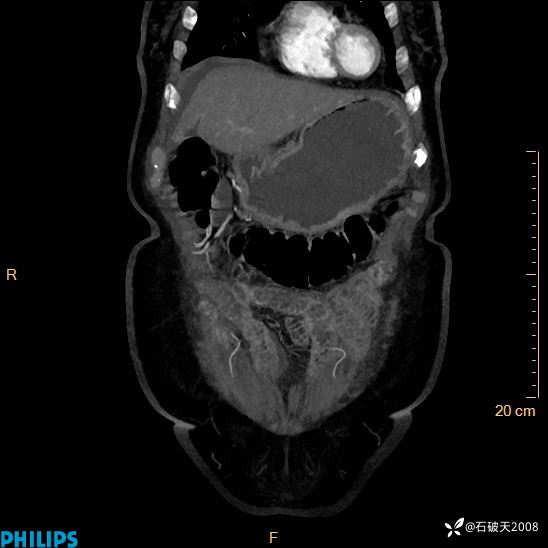

MIP